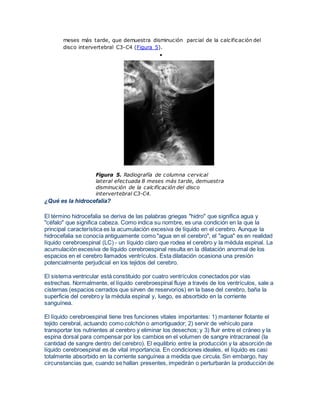

 Se obtiene resonancia magnética (RM) de columna cervical que muestra la

gruesa calcifcación del disco intervertebral C3-C4, con un canal raquídeo de

amplitud normal y médula espinal de morfología y señal normal (Figura 3). La

mielografía por RM no demuestra evidencias de estenosis raquídea (Figura 4).

Fi gura 3 . Imágenes sagitales de RM de columna cervical,

ponderadas en T1 (a) y T1 post-GAD (b). calcificación

hipointensa del disco intervertebral C3-C4 y deformidades

vertebrales adyacentes, sin evidencias de refuerzo patológico en

secuencias post-GAD.

Figura 4. Mielografía por RM de

la columna cervical sin evidencias

de raquiestenosis.

 Catorce días más tarde, la paciente se encuentra totalmente asintomática y

reifere que no ha vuelto a presentar molestias. Se efectuó control radiológico 8

meses más tarde, que demuestra disminución parcial de la calcificación del

disco intervertebral C3-C4 (Figura 5).

Figura 5. Radiografía de columna cervical

lateral efectuada 8 meses más tarde, demuestra

disminución de la calcificación del disco

intervertebral C3-C4.